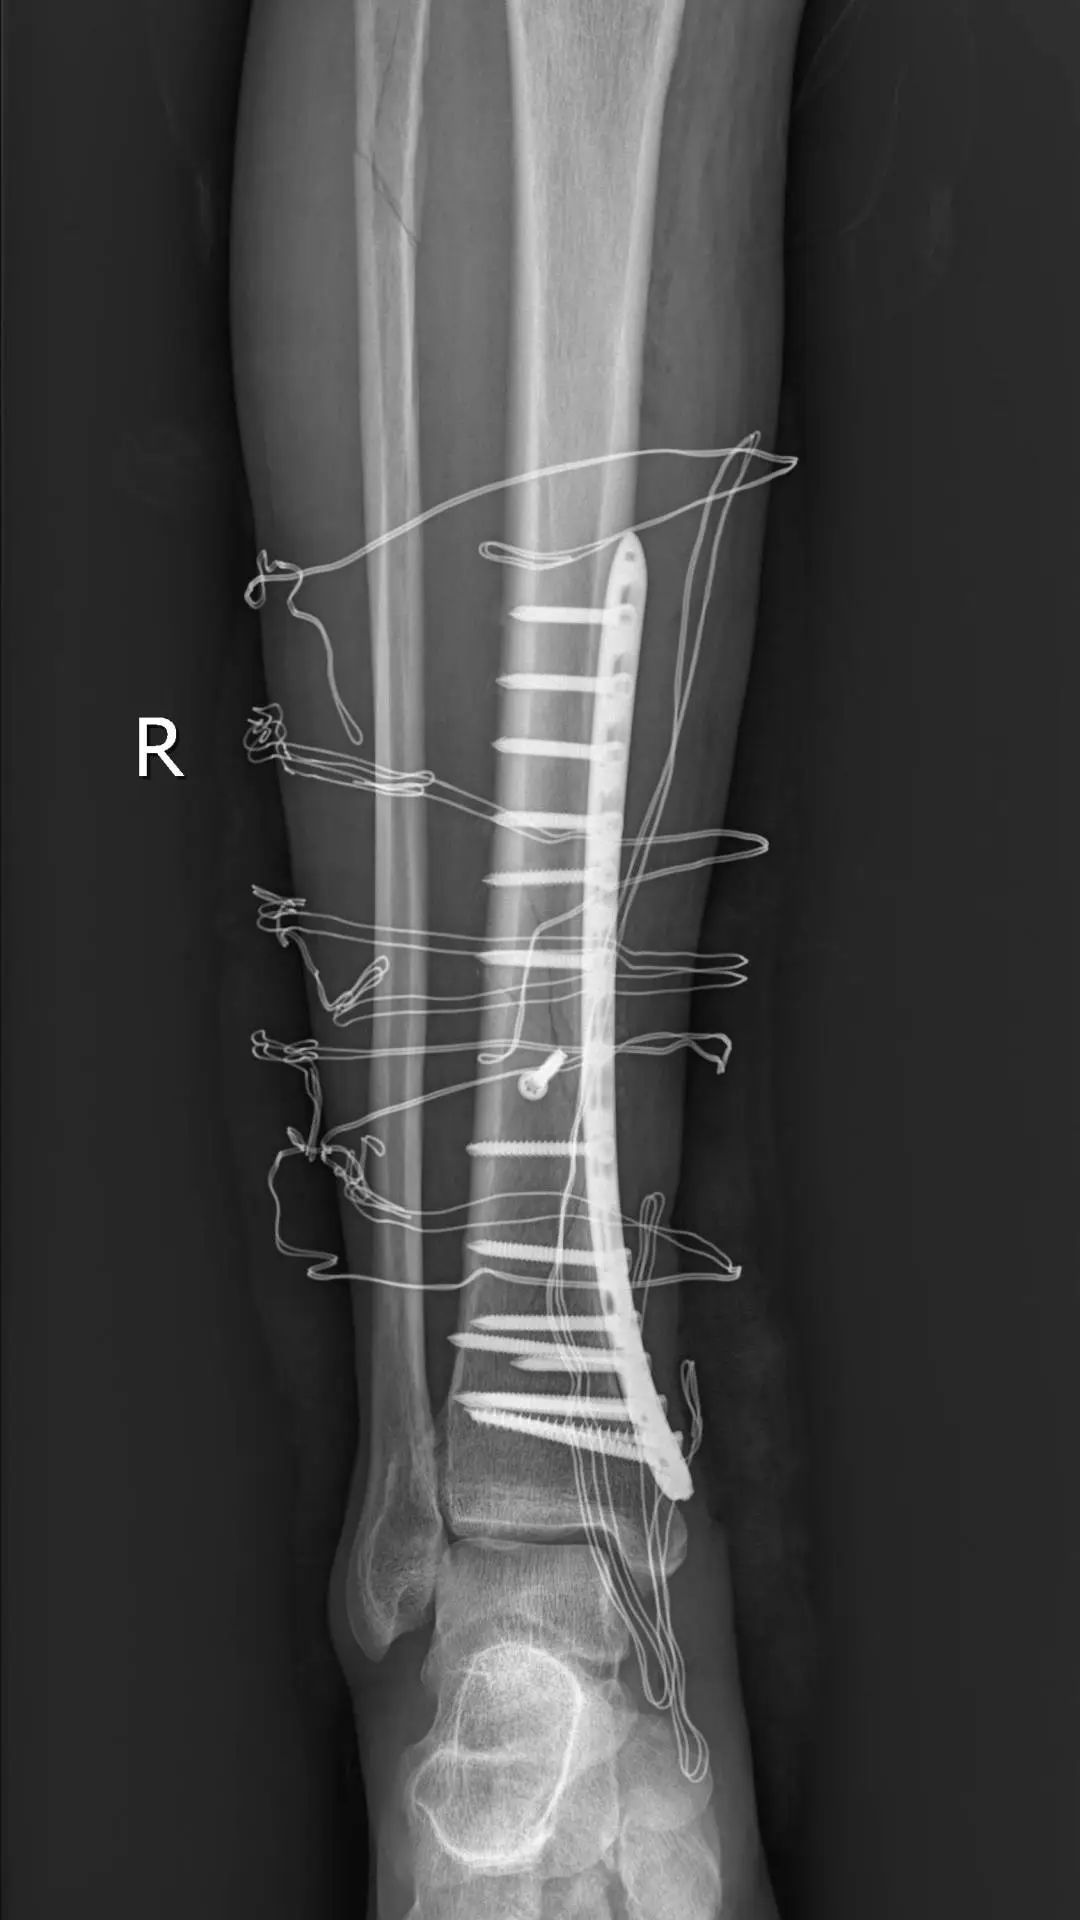

在麻醉科、手术室的密切配合下,仅1小时10分钟,手术顺利结束。

如果按照传统的手术方法做多段的胫骨骨折,切口是从最高点的骨折端到最低点的骨折端,感染的风险增加,对周围软组织的损伤,会遗留明显的疤痕。微创手术的优点

创口小,出血少:

切口仅几厘米,减少了对周围组织的损伤。

恢复快,并发症少:

术后疼痛轻,感染风险低,患者可以早期进行康复功能锻炼。

疤痕小,美观:

小切口愈合后疤痕不明显,更符合美观需求。